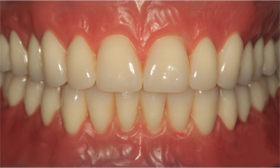

An overdenture in a patient's mouth